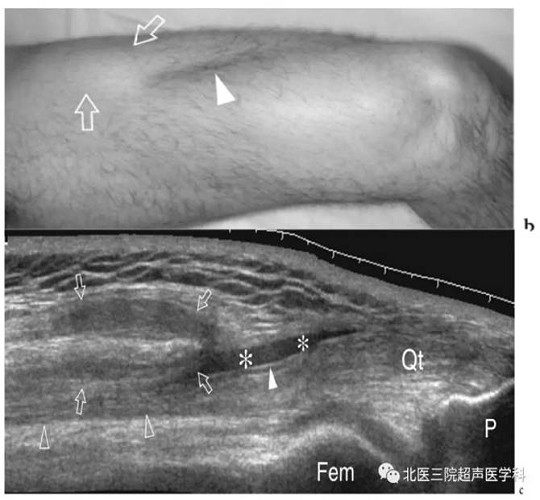

股直肌损伤愈合期(晚期)。患者有股直肌肌腱拉伤史,a长轴宽景成像、b短轴切面,均显示肌肉内中心腱旁的模糊斑点状高回声区,代表残留的瘢痕组织,通常在严重创伤或从事体育活动过早的病例中,c为相应的T2加权轴向的梯度回波成像